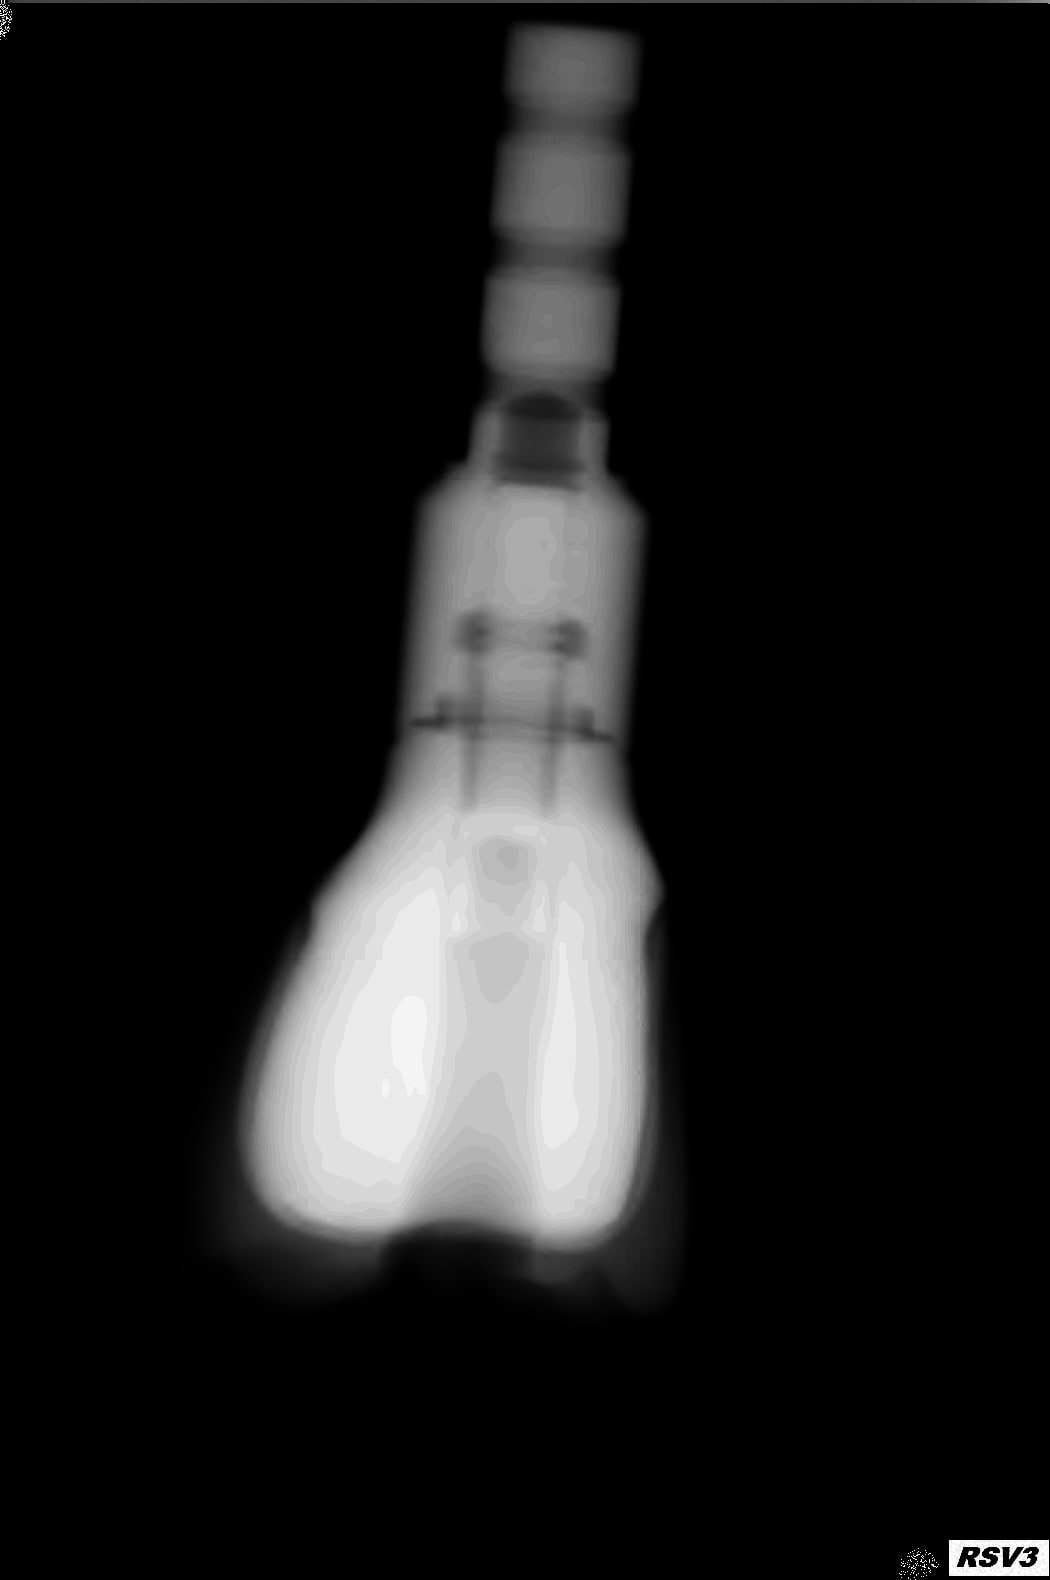

Ci-joint les radio de la 36 sur un analogue qui ne s'ajuste pas malgré un serrage à fond. dans l'implant

361 p7mvhq - Eugenol

362 voepib - Eugenol